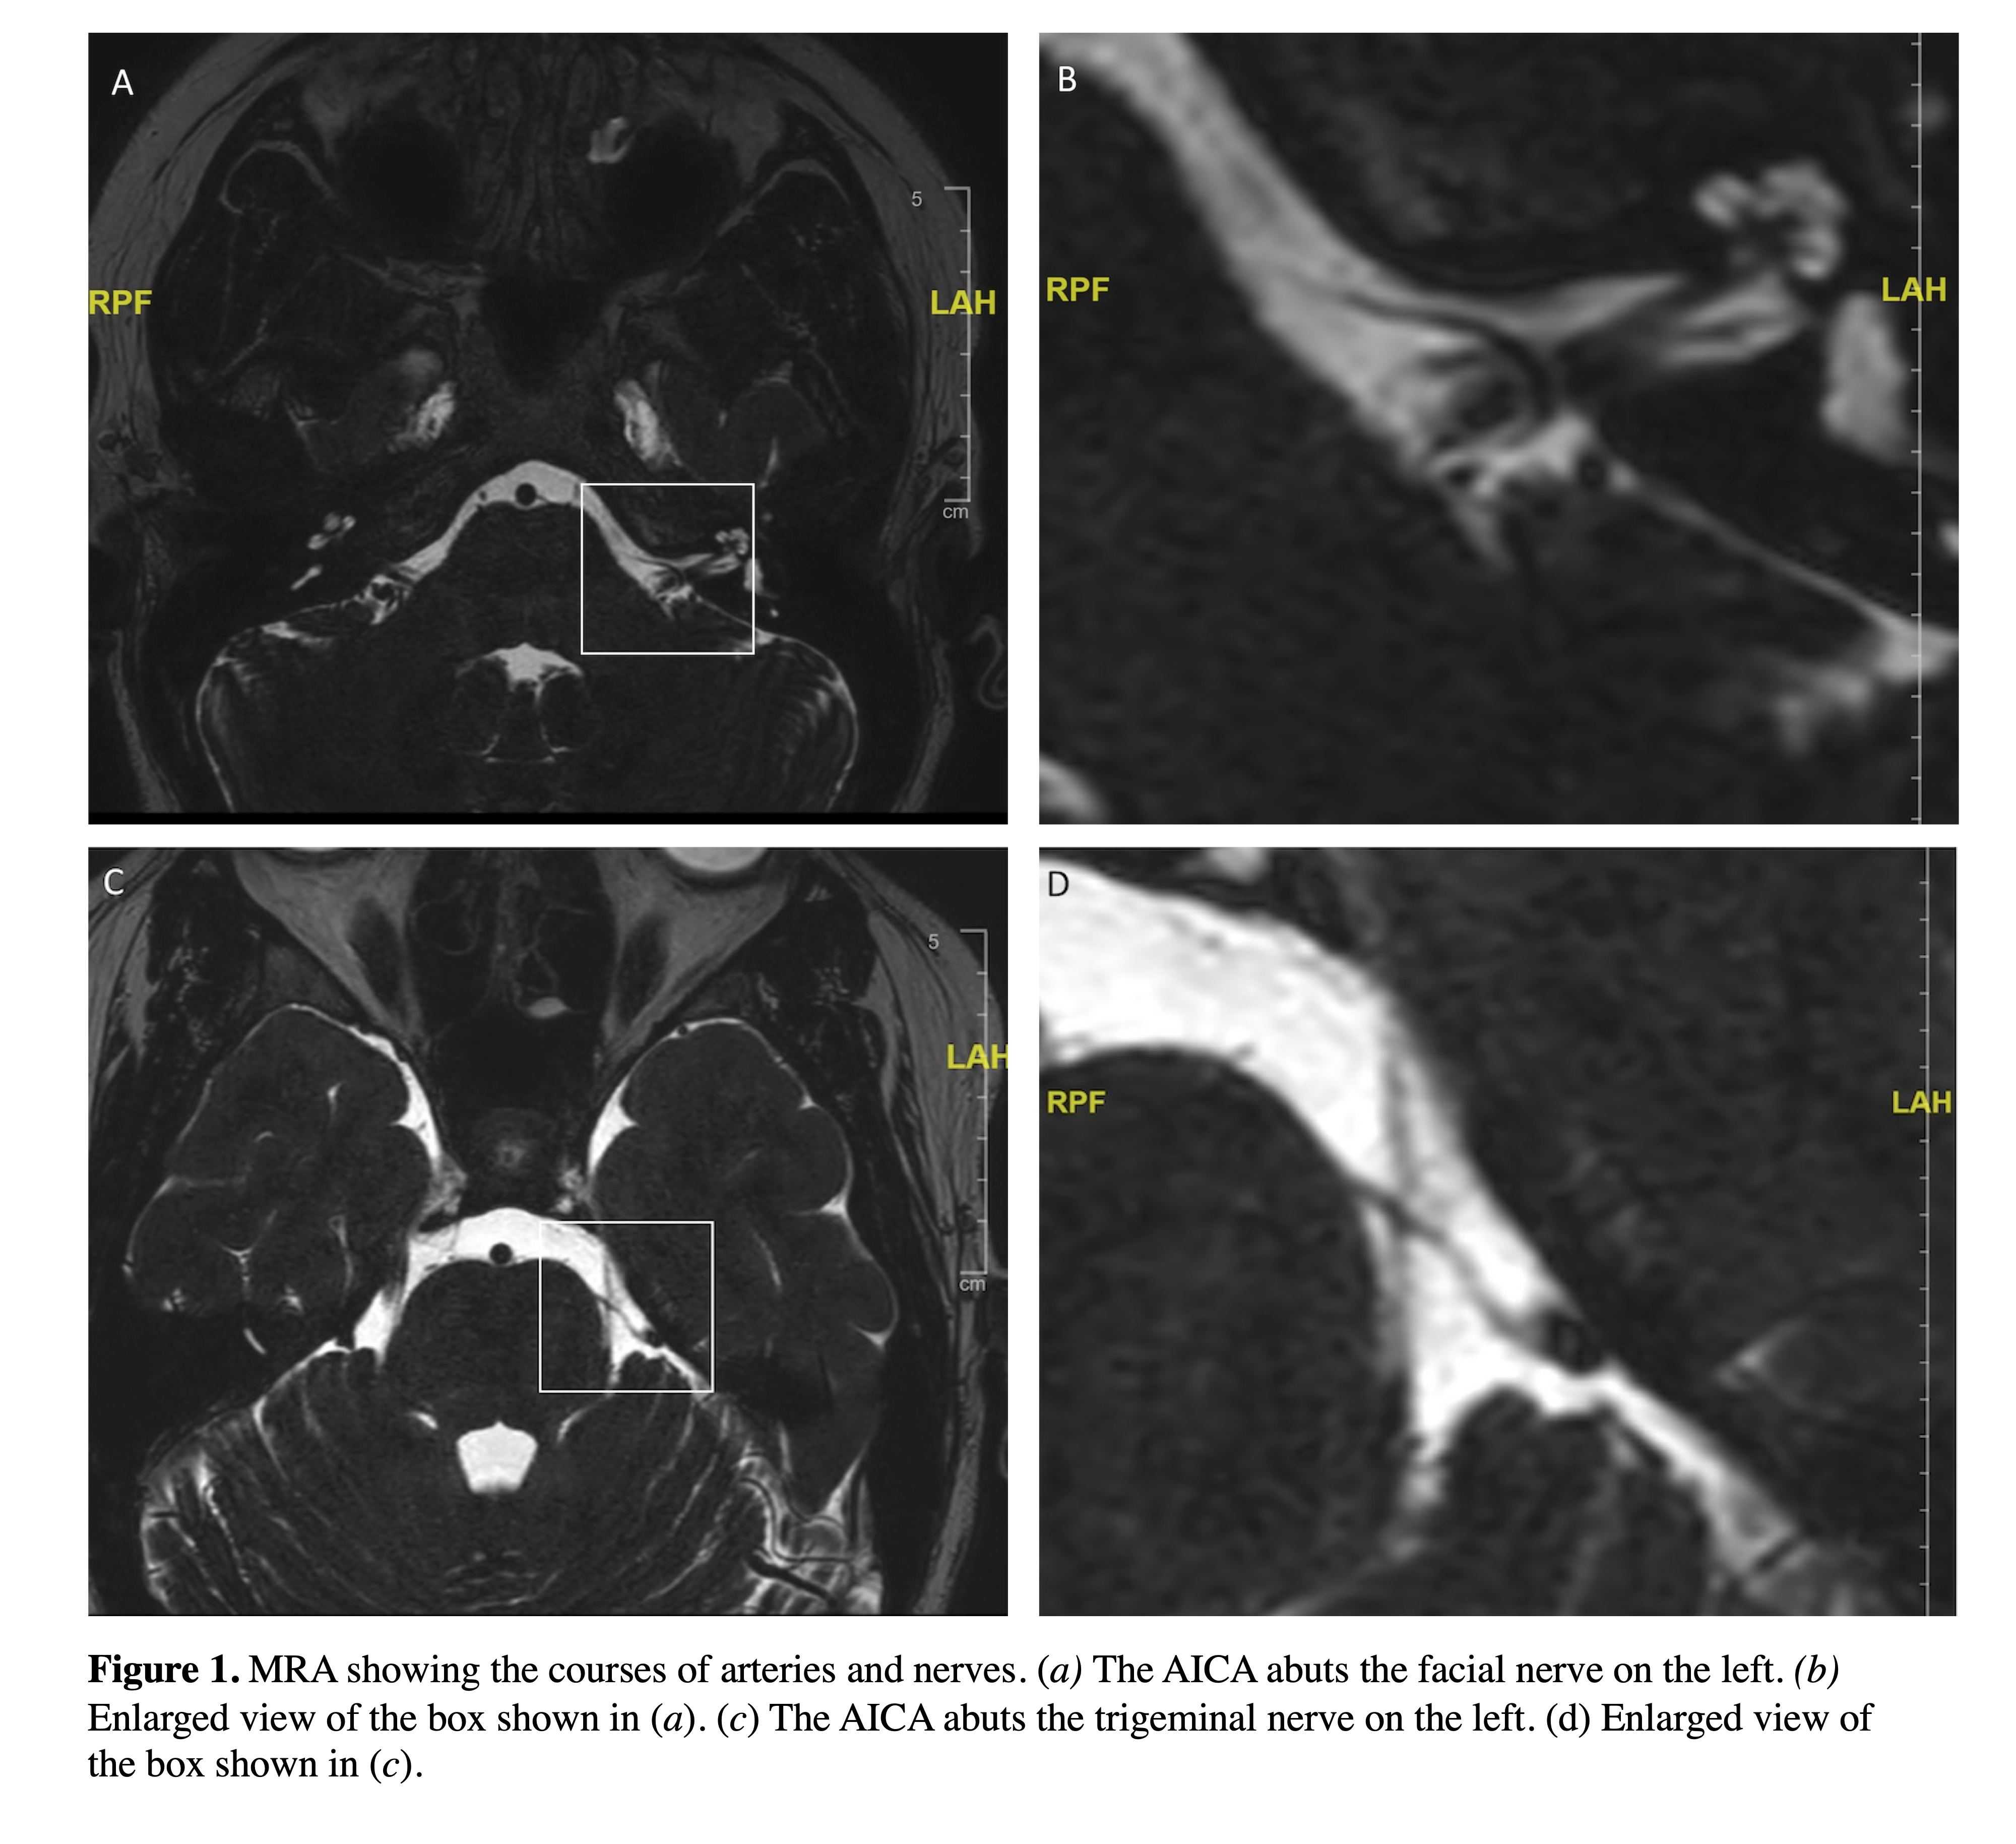

Method: A 29-year-old female presented with intermittent left HFS provoked by lying prone, lifting weights, eating, or drinking. She experienced a flapping sound, shooting pain, and numbness on the left during episodes. An episode was induced in office by lying prone which lasted 3-4 minutes. A repeat MRA revealed that the anterior inferior cerebellar artery (AICA) abutted both the trigeminal and the facial nerves on the left side [Figure 1]The AICA was also noted to abut the right facial nerve. Left retrosigmoid craniotomy was performed with decompression of the left facial nerve. She then experienced worsening HFS on the right which was not position-dependent. Decompression was performed on the right.

figure 1